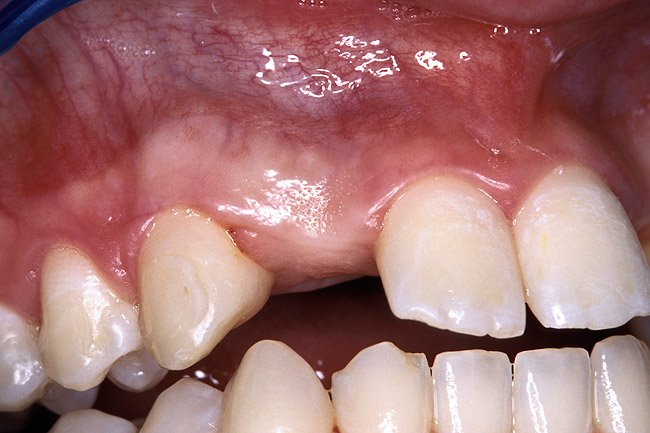

Periapical radiographs were taken to help determine the mesial-distal inclinations of the adjacent tooth roots (Figure 1). The radiographs revealed a serious issue, convergent roots for the right canine and right central, which eliminated that area as a potential implant-receptor site. The space between the left central and canine teeth was minimal, although the roots were relatively parallel. Clinical examination (manual palpation of the root eminences superiorly to the vestibule on the right side) confirmed the root convergence (Figure 2A). The flat, wide zone of the keratinized tissue and lack of interdental papilla was evident for the missing right lateral incisor. There was a marked difference in clinical appearance for the left lateral, which could impact the eventual plan of treatment (Figure 2B). Other significant clinical findings included bilateral facial bone concavities, which existed as a result of the congenitally missing tooth roots. As a diagnostic cue to the underlying bone topography, it is important to follow the demarcation between attached and unattached gingival tissue, and note the crestal width of the available keratinized tissue (Figure 2C).

Figure 2a  Pretreatment buccal views showed (A) root convergence, (B) a difference in clinical appearance of the left lateral, and (C) significant crestal width of keratinized tissue.

Figure 2a

Figure 2b  Pretreatment buccal views showed (A) root convergence, (B) a difference in clinical appearance of the left lateral, and (C) significant crestal width of keratinized tissue.

Figure 2b

Figure 2c  Pretreatment buccal views showed (A) root convergence, (B) a difference in clinical appearance of the left lateral, and (C) significant crestal width of keratinized tissue.

Figure 2c